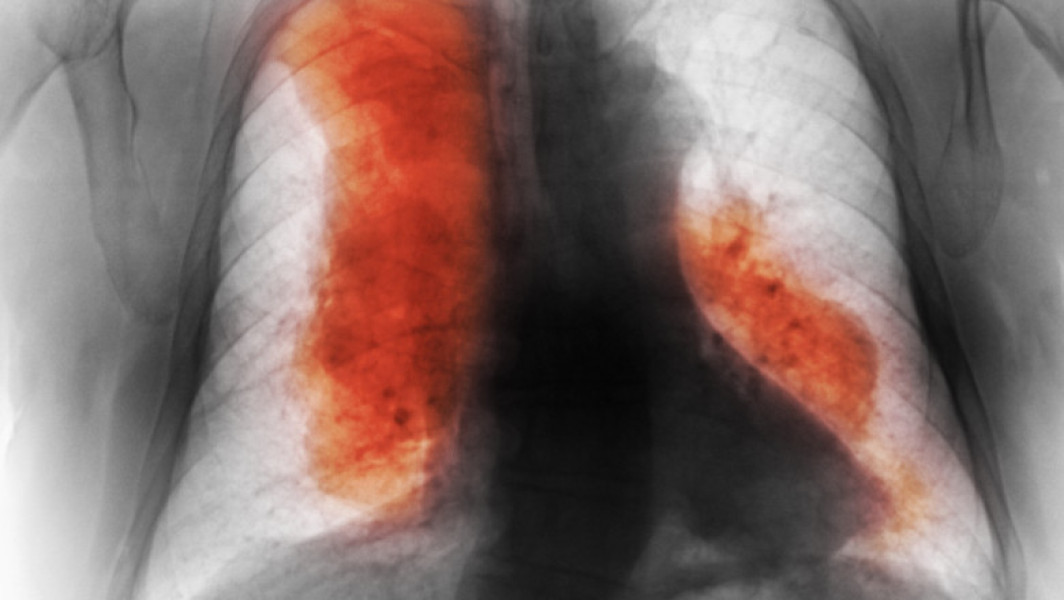

Principalul factor al acestei creșteri este îmbătrânirea populației și majorarea populației globale, în special în țările cu venituri mici și medii, unde se înregistrează cele mai multe cazuri noi. Studiul menționează că în prezent cancerul mamar este cel mai frecvent diagnosticat, în timp ce cel pulmonar rămâne principala cauză de deces.

Conform analizei, numărul cazurilor noi de cancer la nivel global ar putea crește cu 61% până în 2050, atingând 30,5 milioane, iar decesele ar putea ajunge la 18,5 milioane pe an. Deși cifrele au o marjă de incertitudine din cauza lipsei unor date solide și a impactului unor factori recenti, studiul lansează un apel clar pentru intensificarea eforturilor la nivel global în lupta împotriva cancerului.